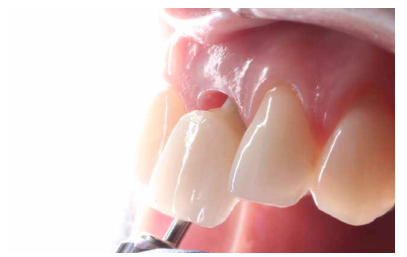

En la región del ICSI, se puede observar una mucosa eritematosa, que se acompaña de la inflamación de la región apical del diente a nivel de la encía insertada y que puede tratarse de un absceso periapical derivado de la infección de dicho diente (Figura 1). El ICSI presenta gran movilidad debido a una fractura radicular que no se puede observar a la exploración clínica.